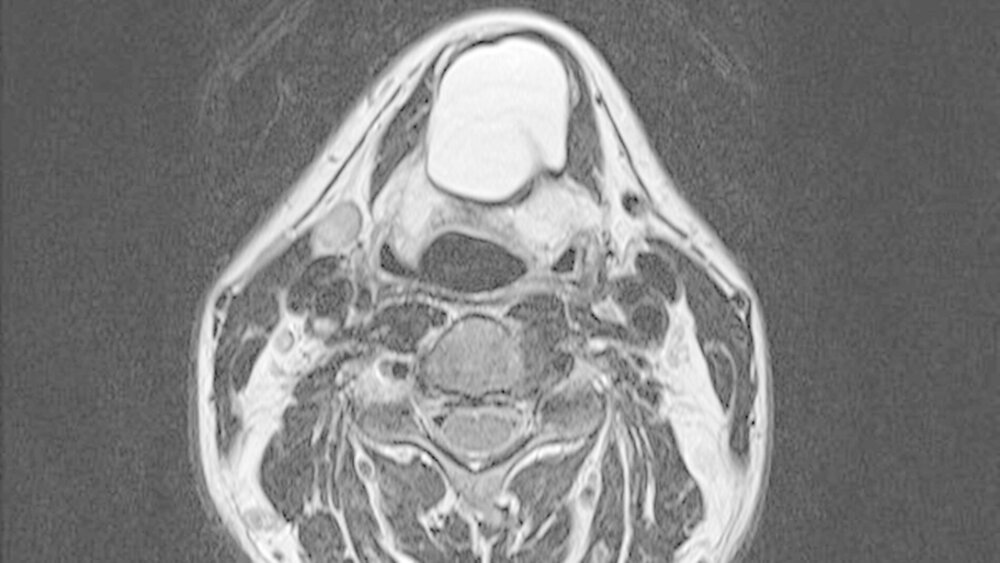

Die unter ambulanten Bedingungen angefertigte schnittbildgebende MRT-Untersuchung des Halses zeigte eine 41x35x27 mm große, gut abgrenzbare, und abgekapselte Raumforderung mit homogener Binnenstruktur. Die Dichtewertemessung wies anhand der Verteilung der Hounsfield-Einheiten einen mit flüssigkeits-äquivalentem, gefüllten Hohlraum auf (Abbildung 2a). Dieser war mit einer mittigen Einschnürung in der Medianebene des Halses und in der Mitte des Os hyoideum lokalisiert (Abbildung 2b). Dabei wird die Verdrängung des aerodigistiven, benachbarten Raumes sowie die Anhebung des Mundbodens und der Zungengrundmuskulatur deutlich (Abbildung 2c).